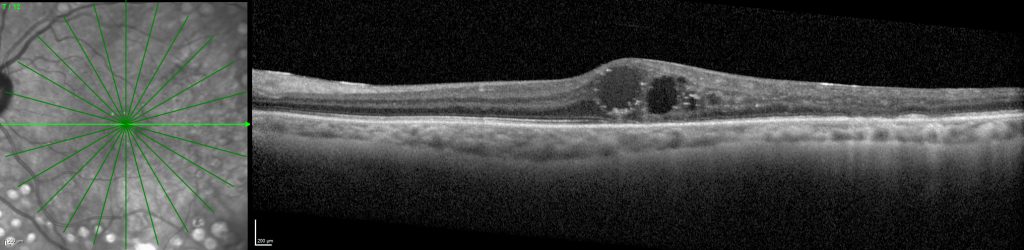

A personas que presenten Edema Macular Diabético y que aún no han recibido tratamiento previo específico para dicha patología. Una vez evaluado el caso, desde la Unidad de Retina y Vítreo del Hospital La Arruzafa explicará al paciente el estudio y se evaluará si cumple con todos los requisitos para poder entrar en el ensayo.

Se trata de un ensayo clínico desarrollado en varios centros a nivel internacional que evalúa la eficacia y seguridad del fármaco en investigación, en comparación con otro tratamiento ya existente. Su duración es de 1 año.

Evaluar la eficacia y seguridad de un medicamento en investigación en comparación con uno de los tratamientos actuales.